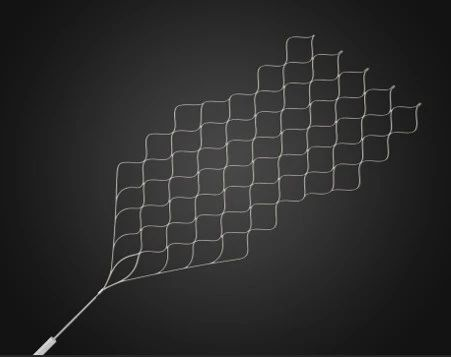

蛟龙取栓支架作为国产取栓支架,在设计上具有其独特的特点,在经典的卷曲式设计的基础上,加入了S形侧边螺旋上升结构,该项发明专利技术使支架夹持血栓能力更强,术中开通率更高以及远端栓塞事件更少。本文介绍了一例颈内动脉闭塞取栓的病例,同时分享一些高负荷血栓取栓的经验。

支架:通桥取栓支架4.0×20mm、6.0×30mm。

该病例提示通桥取栓支架不仅可以应用于常规支架取栓,在双支架取栓应用中,也能取得较好效果。

针对本例患者,选择了单纯使用导引导管的双支架串联式释放同时局部并联释放技术,双重支架叠加可以增加支架释放的径向支撑力,同时也增加了支架网丝对血栓的嵌入效应、接触面积和血栓的缠绕能力,快速将血栓拉出体外,提高了开通效率,并最终获得良好开通效果和3个月良好预后。